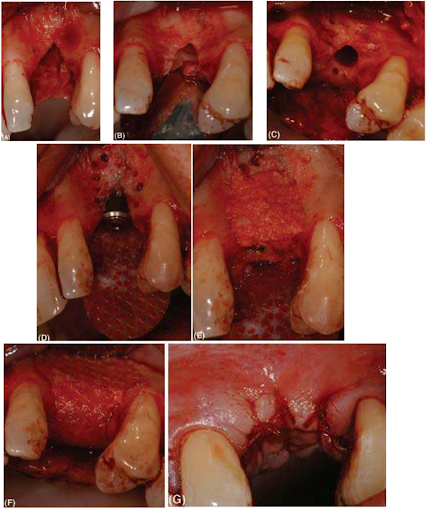

Một loạt hình ảnh lâm sàng cho thấy việc kiểm soát một vết nứt nhỏ. Điều này được thực hiện để cải thiện profile sống hàm và giảm thiểu khả năng implant bị thấy xuyên qua lớp nướu mỏng. (A) Vùng răng nanh trên bên trái mất xương đáng kể chiều cao mào xương và chiều rộng ngoài trong. (B) Vùng đã được chuẩn bị cho một implant Astra Tech 4,5 ST chấp nhận lộ bề mặt implant ở vùng cổ. (C) Xương xung quanh được đục lỗ với mũi khoan tròn. (D) Implant bị lộ bề mặt. Một màng tự tiêu Resolut (WL Gore & Associates Inc.) đã được cắt để che khoảng trống ngoài và trong. (E) Vụn xương thu được từ vùng khoan xương được ép chặt trên vùng implant bị lộ. (F) Màng được tạo hình trên sống hàm để duy trì profile sống hàm mong muốn- màng được nâng đỡ ở ngoại vi bởi xương khỏe mạnh và ở bên dưới nhờ implant và vụn xương. (G) Khâu kín với chỉ tự tiêu.